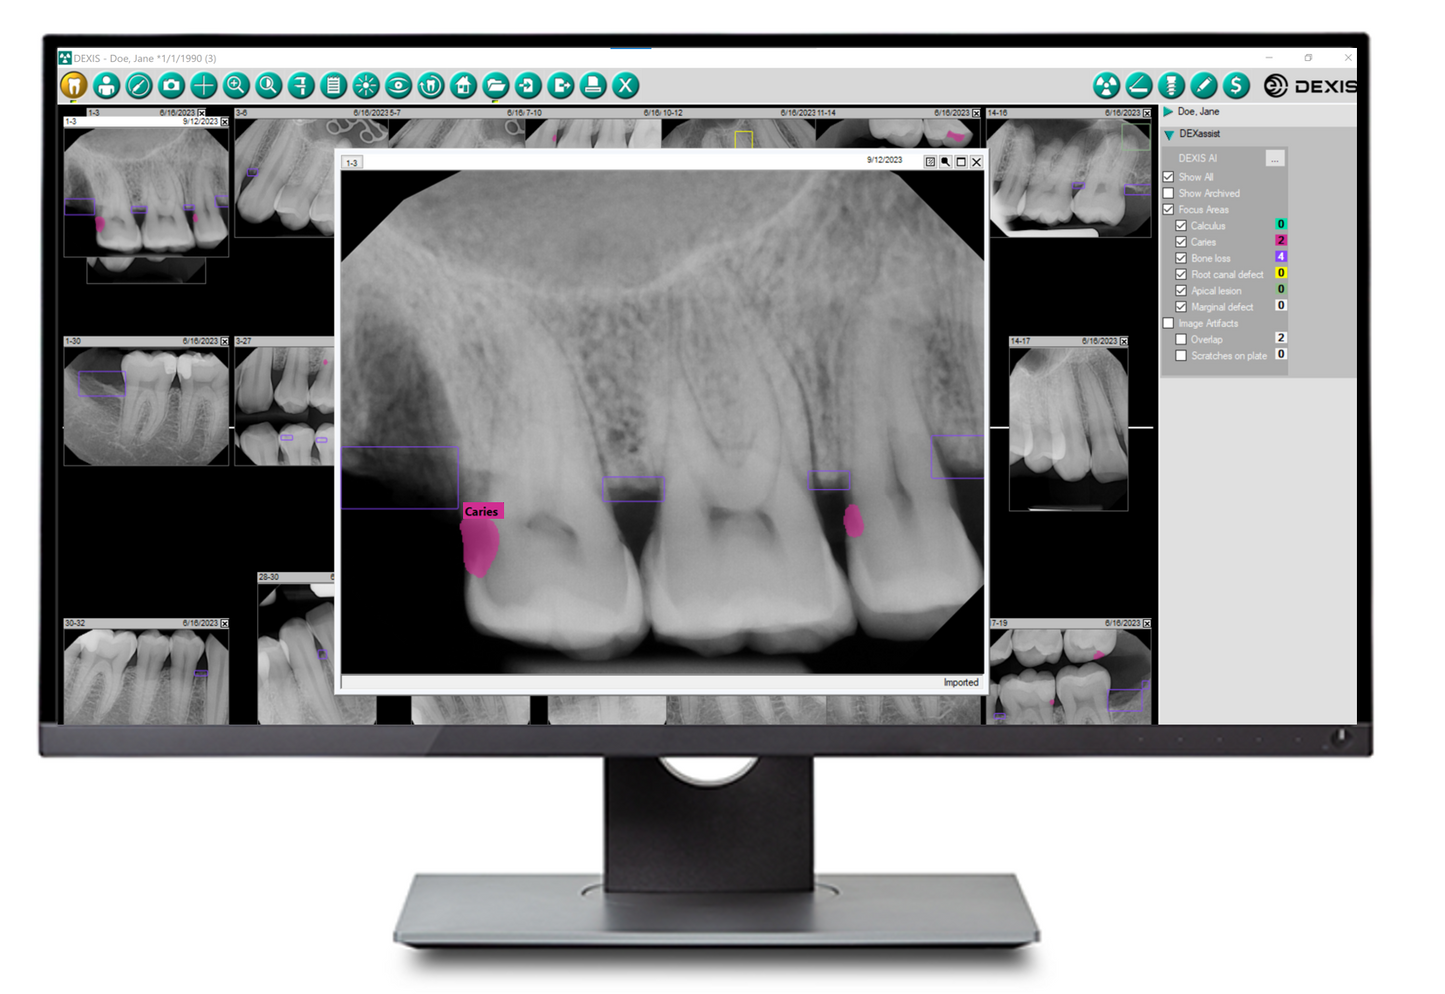

Built into DEXIS™ Imaging Suite Software, the DEXassist Solution provides assisted intelligence with a single click. This new solution enables users to identify up to six dental findings on 2D x-ray images.

The DEXassist Solution integrates AI features from DTX Studio™ Clinic into DEXIS Imaging Suite Software.